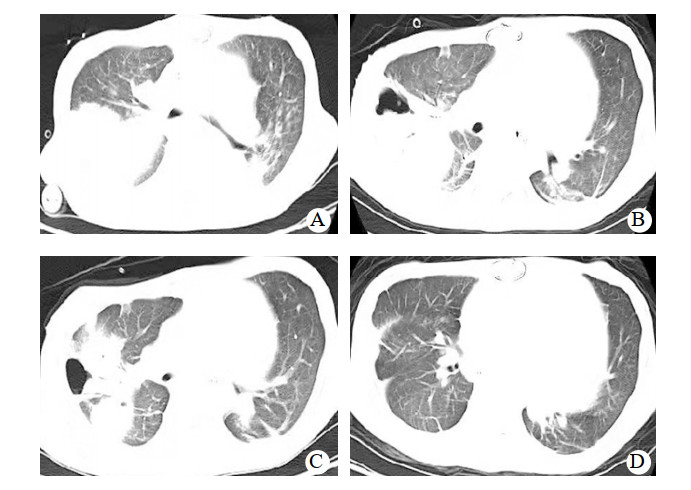

入ICU后查体:血压82/67 mmHg,心率120次/min, 体温36.5℃,呼吸12次/min。双侧瞳孔等大等圆,对光反射迟钝;口唇无发绀,双侧呼吸音粗糙,未闻及干湿啰音。监护提示:窦性心律,心律齐。心前区未闻及心脏杂音;腹平软,肝肋下未触及,肠鸣音弱。四肢末梢皮温正常,足背动脉搏动可及。留置纵隔、心包引流管。入科后即给予了呼吸机辅助呼吸,通气模式采用SIMV/PSV,压力支持12 cmH2O(1 cmH2O=0.098 kPa),呼吸频率12次/min,呼气末正压5 cmH2O, FiO2 0.5,给予舒芬太尼联合右美托咪定镇痛镇静治疗,应用头孢呋辛钠预防切口感染治疗,应用肝素和华法林钠抗凝治疗以及营养支持等综合支持治疗,患者循环稳定,胸片肺淤血较术前减轻,痰不多,于术后第4天顺利脱机拔管,拔管后自主呼吸稳定,少量白稀痰,胸片未见明显变化。术后第7天患者出现体温升高,最高体温38.5℃,痰量增多,为白粘痰,痰中带血,双肺听诊散在痰鸣音,脉搏氧饱和度下降至90%,血气分析提示PaCO2 42 mmHg,PaO2 59 mmHg,实验室检查,PCT 77.87 ng/mL,CRP 198.5 mg/L,患者血压下降,伴有少尿,胸片提示肺感染,经多学科会诊后除外其他部位感染,考虑患者术后合并重症肺炎、呼吸衰竭、感染性休克、急性肾损伤,遂给予再次气管插管机械通气治疗。同时为充分引流痰液,给予了俯卧位通气联合支气管镜肺泡灌洗治疗(俯卧位时间为每次12 h,支气管镜肺泡灌洗每日1次,灌洗剂量为生理盐水100 mL/次),并经验性应用美罗培南联合万古霉素抗感染治疗,给予了液体复苏及CRRT治疗、综合支持治疗。为维持血泵正常运转,继续华林钠口服抗凝治疗,维持INR 2.0~2.5。术后第8天痰培养和血培养均报告为耐碳青霉烯肺炎克雷伯菌,抗生素更改为头孢他啶- 阿维巴坦抗感染治疗。并于术后第15天给患者进行了气管切开治疗。头孢他啶阿维巴坦共应用17 d,期间患者因同时合并了肺部屎肠球菌、热带假丝酵母菌感染,根据药敏实验结果分别给予了替加环素、卡泊芬净等抗感染治疗。因此患者术前反复心衰,营养状况差;术后长期应用抗生素,加上体外循环的打击,机体免疫力差;术后第27天出现菌群失调,严重腹泻,粪便球杆比9 ∶ 1,化验为艰难梭菌感染,给予静脉万古霉素口服(125 mg,q6h)治疗,同时停用所有抗生素。因患者感染未完全控制,继续给予了俯卧位通气联合支气管镜肺泡灌洗治疗,综合营养支持治疗,间断呼吸功能锻炼,患者感染得到有效控制,PCT由77.87 ng/mL下降到0.11 ng/mL,胸片(图 1)及CT(图 2)显示右肺实变影逐渐吸收,术后77 d成功脱离呼吸机辅助,于术后89 d转回普通病房并顺利出院。后期随访患者生活正常。

图 2 患者胸部CT变化